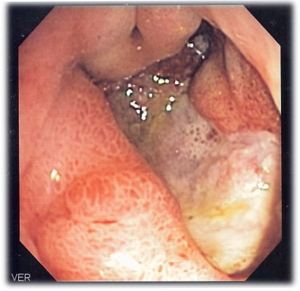

صورة منظارية لقرحة هضمية، الخزعة أثبتت أنها سرطان المعدة.

يتم التأكد من وجود القرحة الهضمية فعلا في الأشخاص المتوقع إصابتهم بها عن طريق استخدام المنظار المريئي المعدي الاثنى عشري (EGD)، أحد أنواع المناظير(المجاويف) الذي يعرف أيضا بالمنظار المعدي، من خلاله يتم تحديد موقع القرحة ودرجة خطورتها، كما أنه يرشد إلى التشخيص البديل في حال عدم وجودها. ويتم تشخيص الإصابة بالملوية البوابية بالطرق التالية: